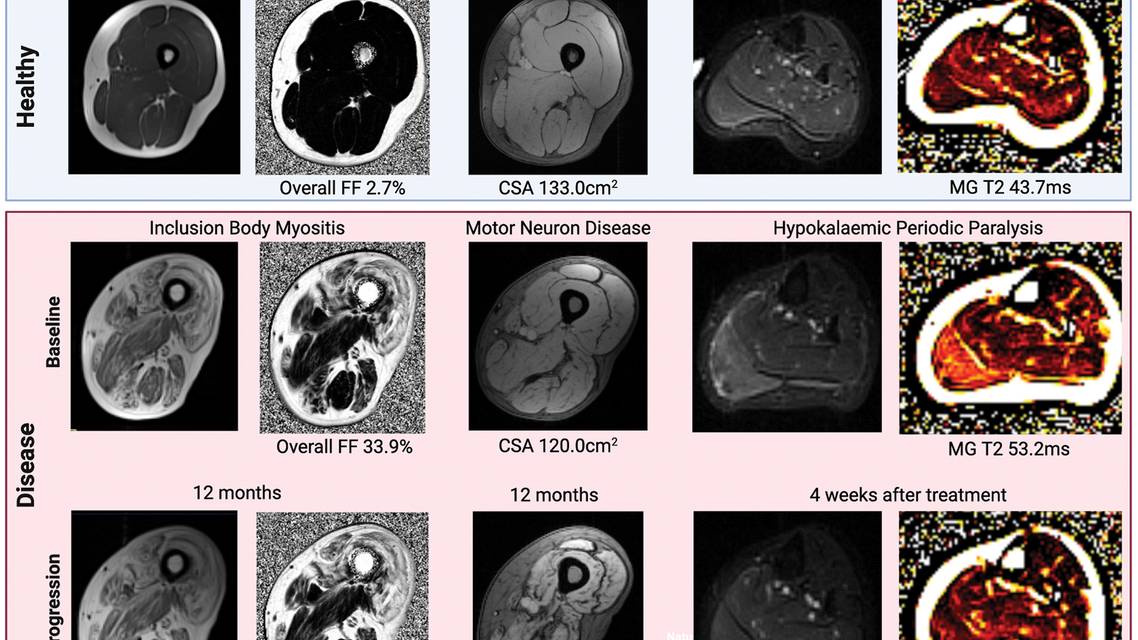

Alternative imaging modalities, such as ultrasound and positron emission tomography, offer complementary advantages. Ultrasound is portable, accessible, and cost-effective, with applications in muscle architecture visualization and functional assessment. However, its operator dependency limits reproducibility compared with MRI. Other imaging modalities are emerging as potential biomarkers for neuromuscular diseases (eg, ultrasound shear wave elastography, functional ultrasound, bioelectrical impedance), but they require further validation for widespread use. The Figure includes examples of multimodal MRI scans.

Figure. Examples of multimodal MRI scans (T1-weighted, T2-weighted, short tau inversion recovery [STIR], and fat fraction [FF] maps) of muscle replacement with fat (T1-weighted thigh and FF maps), muscle size (Dixon acquisition thigh), and muscle edema (T2-weighted STIR calf and quantitative T2 mapping calf). Examples of healthy (blue top row) compared with diseased (red bottom rows) muscle at baseline (red row, top) and interval progression (red row, bottom).

Abbreviations: CSA, cross-sectional area; MG, medial head of gastrocnemius.